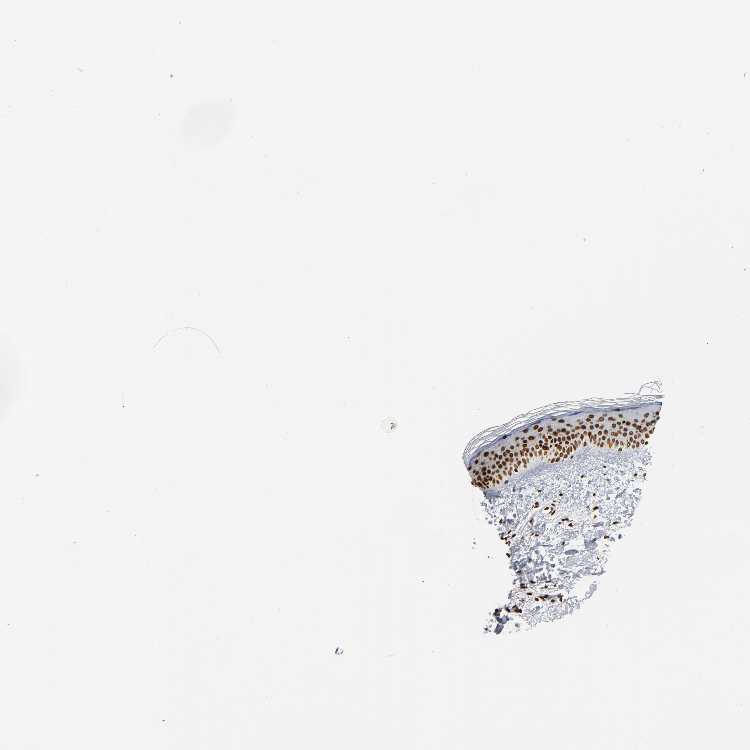

SKIN 1 - Antibody stainingi

Antibody staining in the annotated cell types in the current human tissue is reported as not detected, low, medium, or high, based on conventional immunohistochemistry profiling in selected tissues. This score is based on the combination of the staining intensity and fraction of stained cells.

Each image is clickable and will lead to virtual microscopy that enables deeper exploration of all samples and also displays staining intensity scores, fraction scores and subcellular localization as well as patient and tissue information for each sample.

Antibody CAB004565Antibody CAB005352

Langerhans HighHigh

Fibroblasts HighMedium

Keratinocytes HighHigh

Melanocytes HighHigh

SKIN 2 - Antibody stainingi

Epidermal cells HighHigh